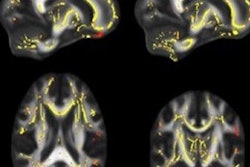

The image was acquired using DTI-MRI by Nian Wang, PhD, assistant professor of radiology at the Center for In Vivo Microscopy at Duke University. The image demonstrates a mouse kidney at 10-micron resolution and has been colorized to represent the orientation of different tubules in the organ that collect filtrate from blood passing through the kidney and process it into urine.

Diffusion-tensor MR image of a kidney at 10-micron isotropic resolution. The image makes it possible to estimate location, orientation, and anisotropy of the tubular tracts; colors represent the different orientation of tubules. Image courtesy of BMC.The Duke center focuses on developing novel MRI methods for detecting tissue microstructures, according to a statement released by BMC. Researchers at the center have found that the nondestructive nature of MRI and its ability to assess renal microstructure in 3D make the modality a promising tool for understanding complex structures.